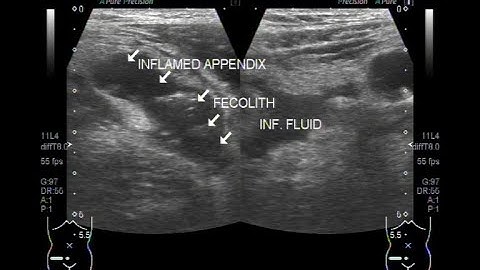

Ultrasound Video showing Inflamed appendix with faecolith in its interior.